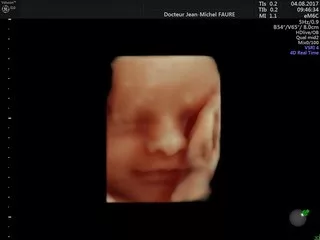

Jean-Michel FAURE

Dr Faure

Tous les examens échographiques sont réalisés avec les échographes les plus récents du marché, mis à jour régulièrement, et sont conformes aux recommandations de bonnes pratiques des sociétés françaises :